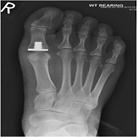

Big toe arthritis presents with pain and stiffness arising from the big toe joint (first metatarso-phalangeal joint) and is often associated with a bump (bone spur) felt on top of the joint (Fig 1). It is usually caused by wear and tear of the joint (arthrosis). This can occasionally be triggered by an injury but usually comes on over several years. The symptoms interfere with activities and can be made worse by a shoe with a tight toe box. Clinical examination and x-rays (Fig 2) confirm the diagnosis.